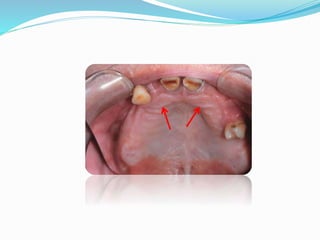

•It is a pad of fibrous connective tissue overlying

the orifice of the nasopalatine canal.

Significance :

1. Stable landmark and gives its relation to

incisive foramen through which the

neurovascular bundle emerge and lie on the

surface of bone.

Incisive Papillae -

2. It is a biometric guide giving information on

positional relation to central incisors which are

about 8-10 mm anterior to incisive papilla.

3. Biometric guide which gives us

information about location of maxillary canines

(A perpendicular drawn posterior to the centre of

incisive papilla to sagittal plane passes through

canines).

Clinical Consideration : During final

impression procedure, care should be taken not

to compress the papilla. Hence the incisive

papilla should be relieved with a spacer.

Reason :

a. Compression of blood vessels obliteration

of the lumen  deprive nutrition to tissues 

breakdown of tissues.

b. Pressure on nerve causes parasthesia in the

region of upper lip.